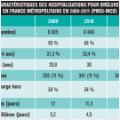

En France, le cancer de la prostate est actuellement la tumeur maligne la plus fréquente chez les hommes (environ 48 000 nouveaux cas par an) et représente plus de 25 % de tous les cancers diagnostiqués à partir de 50 ans. L’incidence du cancer de la prostate a montré une tendance à la hausse constante au cours des dernières décennies, en particulier autour des années 2000, en conjonction avec la diffusion du dosage de l’antigène spécifique de la prostate (PSA) comme outil de dépistage. Ensuite, l’incidence a diminué de façon modérée, en particulier chez les hommes entre 50 et 60 ans. Compte tenu de l’agressivité différente des diverses formes de maladie, le cancer de la prostate occupe la troisième place sur l’échelle de la mortalité corrélée aux cancers, dans presque tous les cas impliquant des hommes de plus de 70 ans (environ 8 000 décès par an). Cependant, les comorbidités qui sont généralement présentes chez les personnes âgées peuvent rendre difficile la séparation des décès pour cause de cancer de la prostate de ceux survenus avec un cancer de la prostate.

En France, le cancer de la prostate est actuellement la tumeur maligne la plus fréquente chez les hommes (environ 48 000 nouveaux cas par an) et occupe la troisième place sur l’échelle de la mortalité corrélée aux cancers (environ 8 000 décès par an).